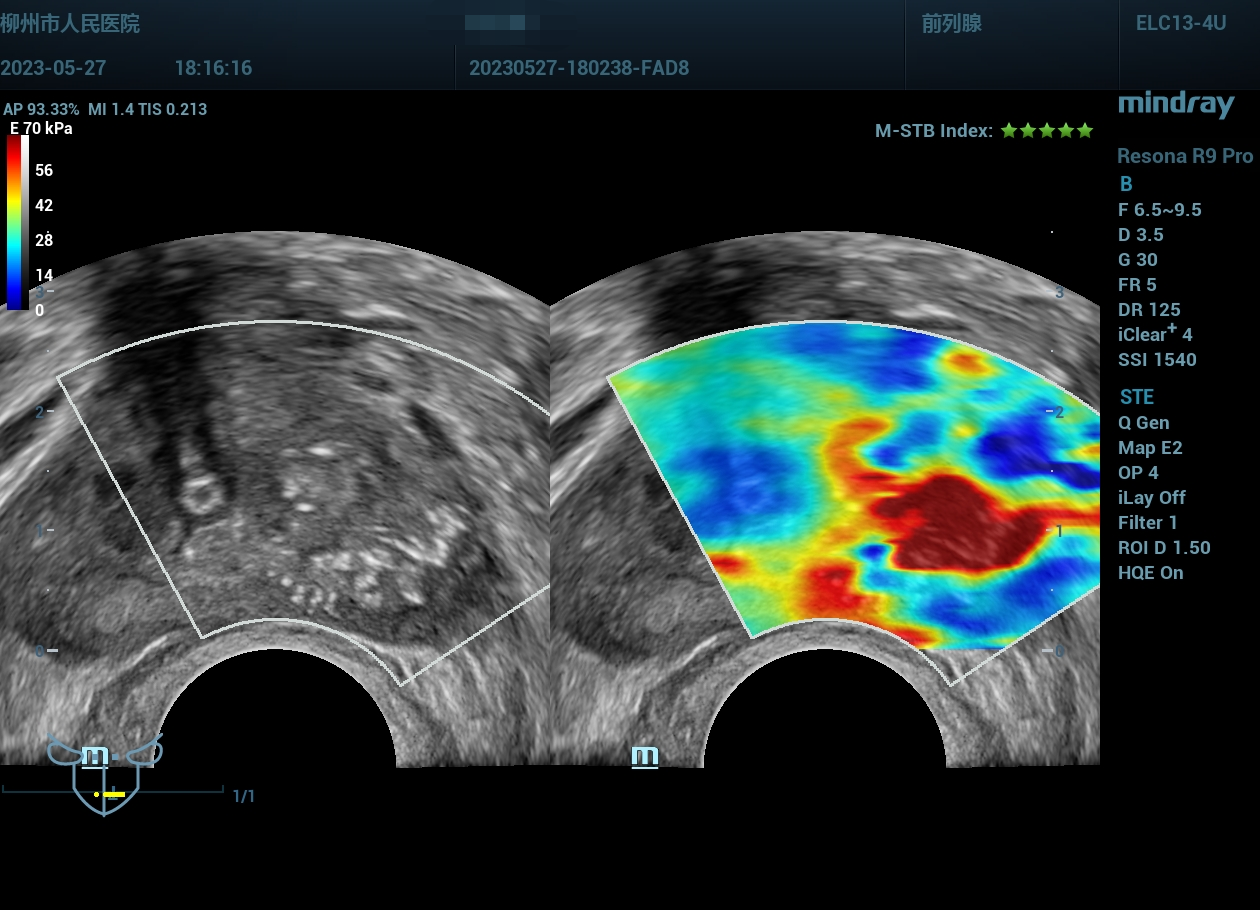

经会阴前列腺穿刺,病例实操(前列腺癌),柳州市人民医院,2023年

老年男性

经会阴前列腺穿刺,病例实操(前列腺癌),柳州市人民医院,2023年-主页丨今日超声